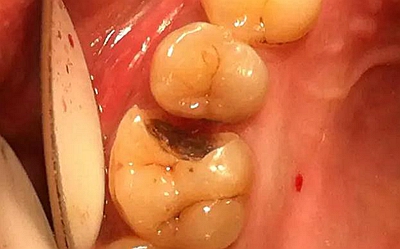

患者女性,55歲,3年前B3纖維樁+鑄瓷全冠修復(fù),一周前牙冠折斷,就診后,發(fā)現(xiàn)纖維樁根管口處折斷,周圍牙齦增生,建議患者行冠延長(zhǎng)手術(shù)。首先去除斷端的纖維樁。拍片示牙根長(zhǎng)度充足。于是開始冠延長(zhǎng)手術(shù)。

因?yàn)槭乔把?,故該患者將?lái)修復(fù)體邊緣必須為齦下,所以3個(gè)月后再行修復(fù)。以下為手術(shù)前照片。

以下為術(shù)中照片。

內(nèi)斜切口,頸圈組織,改良垂直褥式縫合。